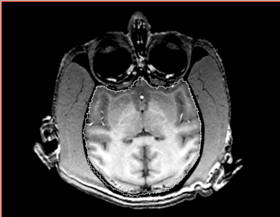

* Correction of the bias in vervet MRI. Acquisition parameters: 3T GE scanner, single-channel dedicated RF coil (Litzcage, Doty Scientific, Columbia, SC); 3D SPGR sequence (TI 600ms, TE 3.276ms, TR 15.28ms; flip angle 15 deg; matrix 256x256; FOV 12cm; in-plane resolution 0.47 mm; slice thickness 0.5 mm). | * Correction of the bias in vervet MRI. Acquisition parameters: 3T GE scanner, single-channel dedicated RF coil (Litzcage, Doty Scientific, Columbia, SC); 3D SPGR sequence (TI 600ms, TE 3.276ms, TR 15.28ms; flip angle 15 deg; matrix 256x256; FOV 12cm; in-plane resolution 0.47 mm; slice thickness 0.5 mm). | ||

| + | |[[Image:n4_mark1_input.png|thumb|280px|Slice of the input test volume with apparent bias field and label outlines]] | ||

| + | |[[Image:n4_mark1_output.png|thumb|280px|Output image visually contains less inhomogeneity]] | ||

| + | |[[Image:n4_mark1_bias.png|thumb|280px|Recovered bias field]] | ||